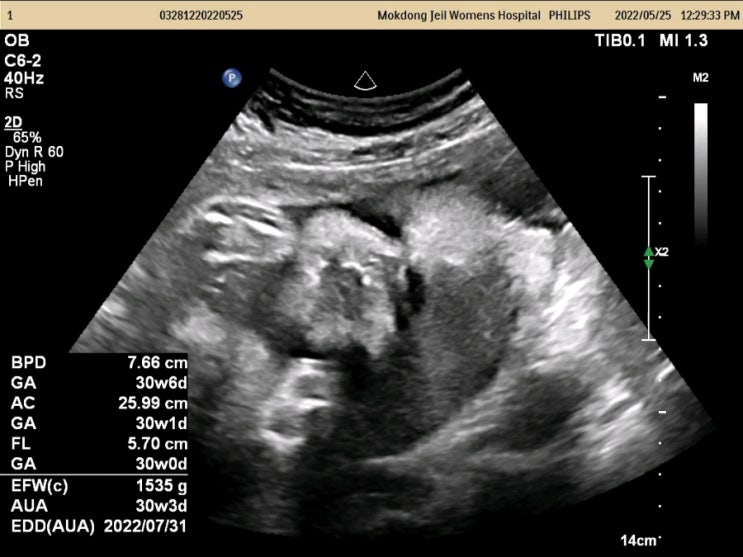

[30주] 자연분만이 어려울수있다구요?!

30주 급 분만방법에 대해 논의하다! 드디어 30주 돌입! 정기검진을 위해 병원에 방문하였다고한다! #목동제...